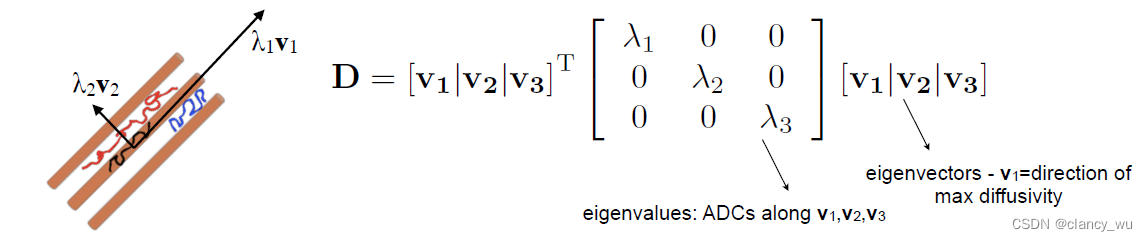

DTI的原理基础是弥散张量模型,Diffusion Tensor Model。即在每一个体素里计算它的

在计算的时候,是按照定义的坐标系进行计算,XYZ坐标系:

其实还需要计算它的解剖学坐标系:

这样,通过这些定义的坐标系,我们就能用公式来表达各向异性和各向同性: